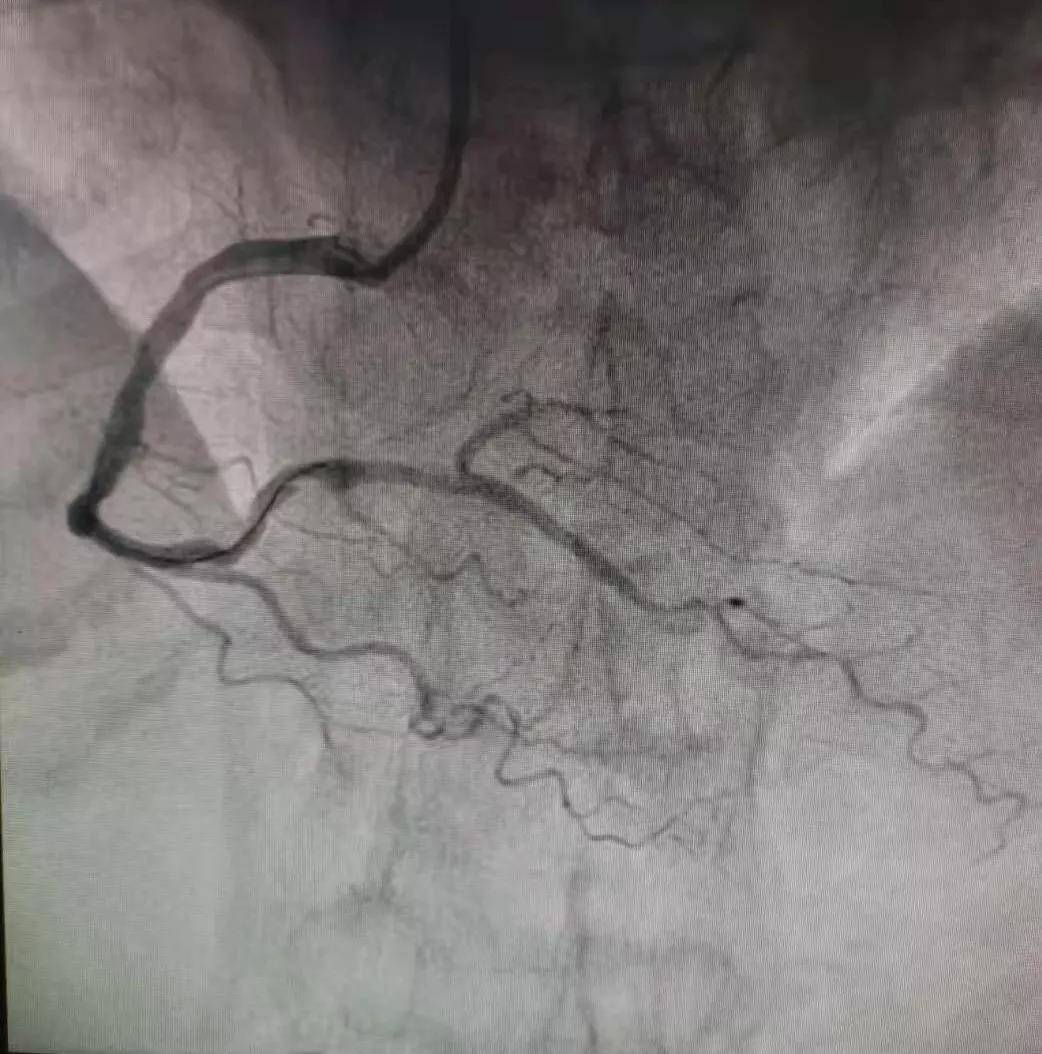

术中冠脉造影提示:患者右冠状动脉远段支架内100%闭塞 , 左冠前降支远端管腔70%狭窄 , 根据患者目前的病情 , 与家属沟通并获得其家属同意后 , 开通闭塞血管 , 给予患者右冠远段支架内药物球囊扩张治疗 , 恢复血流灌注 , 最大程度的挽救了心肌细胞 。